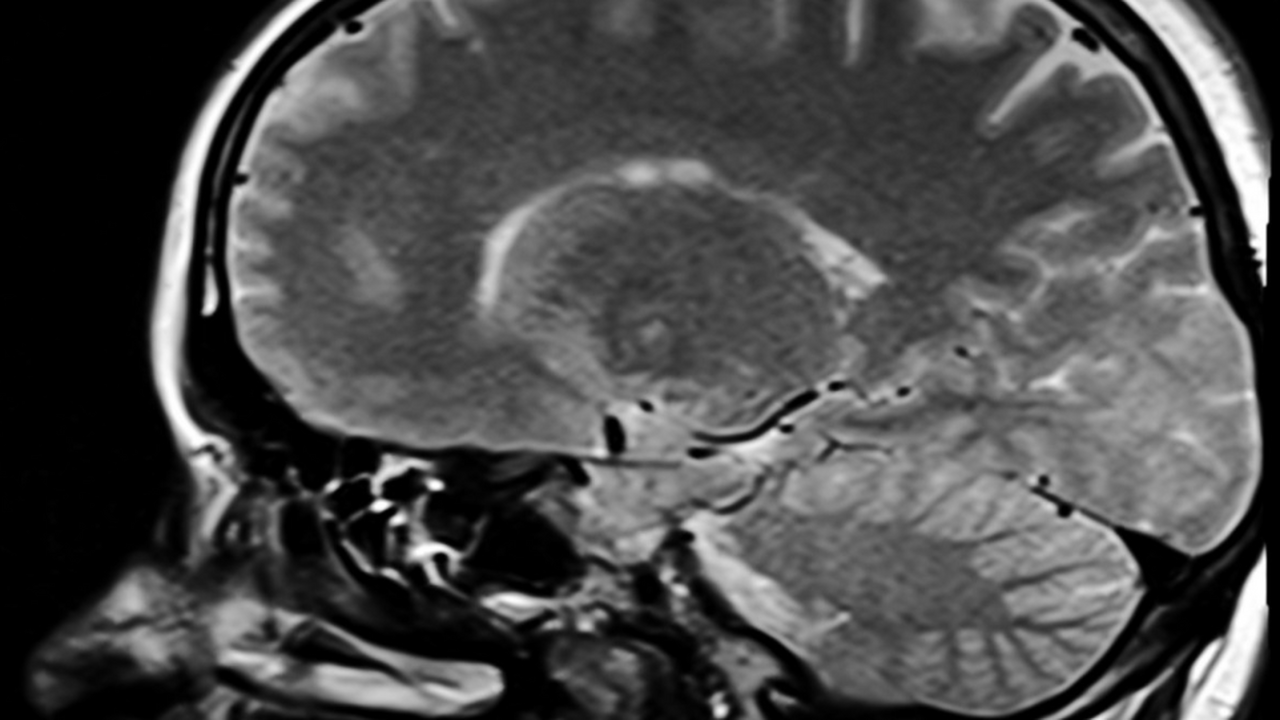

Исследователи из Weill Cornell Medicine обнаружили, что свободные радикалы, образующиеся не в нейронах, а в астроцитах — вспомогательных клетках мозга, — могут способствовать развитию деменции. Как сообщает Nature Metabolism, блокирование этих процессов снижает воспаление мозга и защищает нервные клетки, что открывает путь к новым методам лечения нейродегенеративных заболеваний, включая болезнь Альцгеймера и лобно-височную деменцию.